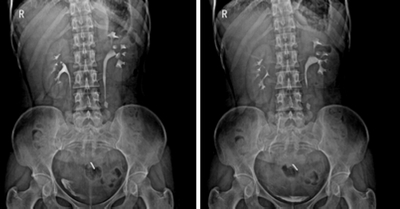

★適用于全身各部位攝影,包括常規(guī)攝影(立位攝影、臥位攝影等,如胸片、頸椎、腰椎、腹部、頭顱、四肢等)和特殊攝影(傾斜攝影、角度攝影等,如瓦氏位、骶髂關(guān)節(jié)、髕骨軸位、跟骨軸位等)。